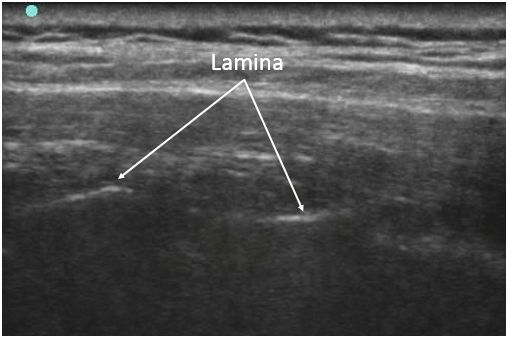

実際のエコー画像をお見せします。

下図は、背部正中線から約1.5cm外側で、脊椎に平行にプローブを当てたものです。

白く光ってみえるのが椎弓版のところです。